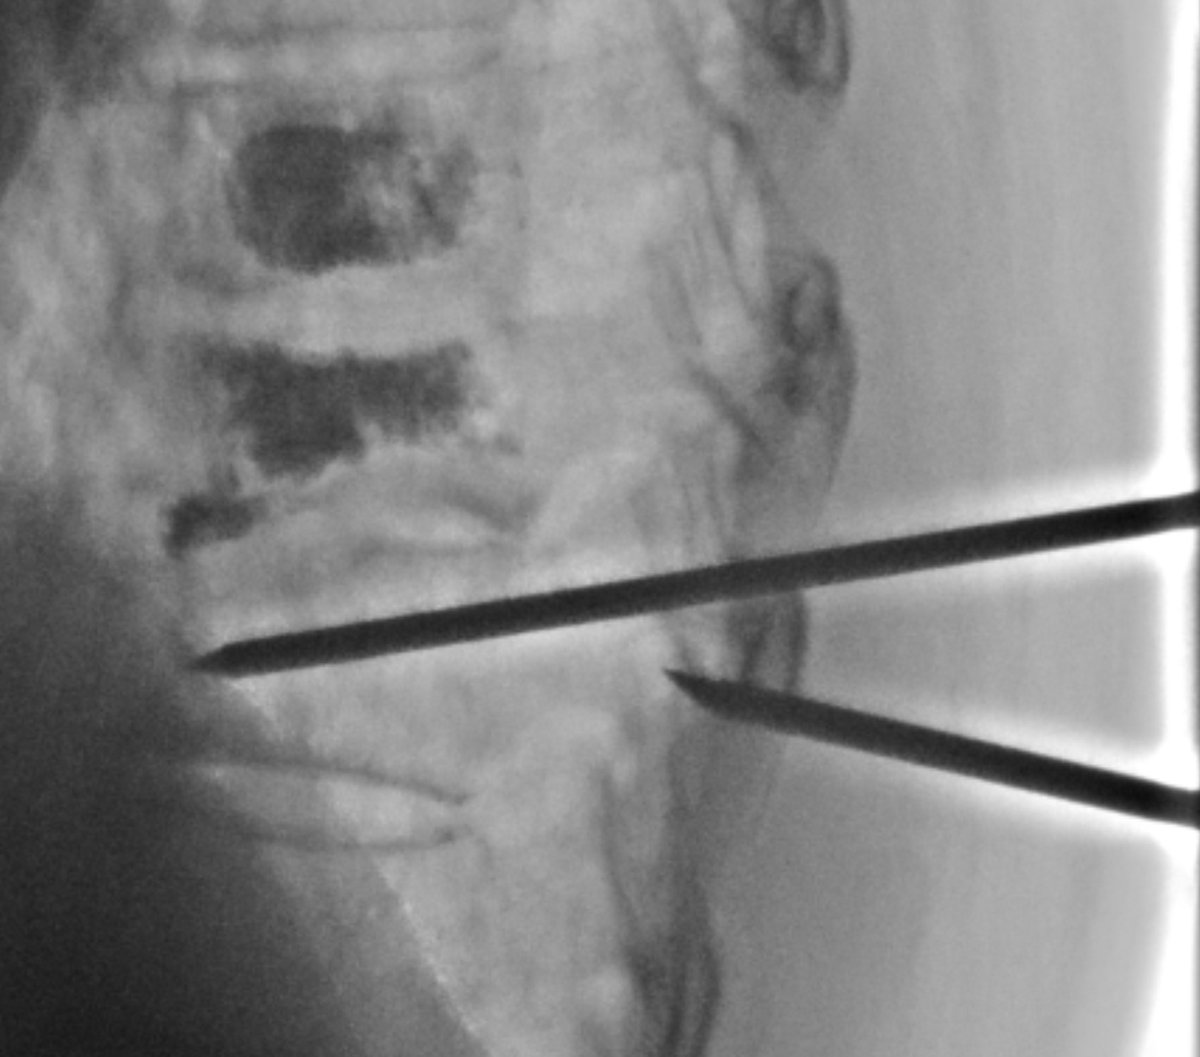

Curved needles and cement cannulas are helpful for targeting focal fracture clefts. Small T8 superior endplate cleft after otherwise sufficient kypho at OSH was not amenable to pedicular access. Transdiscal access from above made for an easy fix.

1. off-label device use. 2. paravertebral extrav at T6 and T7: ugly but clinically insignificant. Usually leak from a fracture line extending to the lateral cortex. Catch it, slow down, let it plug. Proceed. Same for small vein at T6.